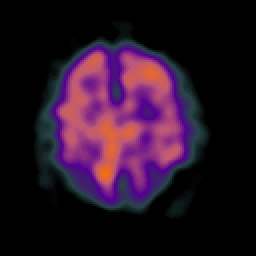

Alzheimer's disease: Perfusion SPECT -- Slice #37

[Home][Help][Clinical][Tour 1][Tour 2] Slice 37